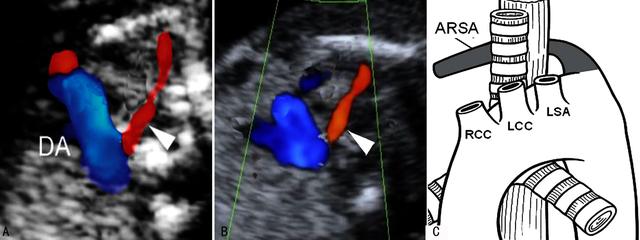

人们曾经认为21-三体综合征胎儿的心脏畸形都是发生在心内 , 随着病例的增加和研究的深入 , 发现心外的异常和大血管的异常也比较常见 , 迷走右锁骨下动脉(aberrant right subclavian artery, ARSA)就是其中之一(图5) 。 大约有30%~36%的21-三体综合征胎儿发生右侧锁骨下动脉的起源异常 。 正常情况下右侧锁骨下动脉起源于头臂干动脉 , 但此时可以直接起源于主动脉弓 , 后者直接发出了4支血管而不是正常的3支血管 。 迷走的右侧锁骨下动脉起源于左侧锁骨下动脉远端的主动脉(图5) 。

图5右侧锁骨下动脉迷走 A、 B:右侧锁骨动脉迷走血流显示(三角箭头) C:右侧锁骨动脉迷走解剖示意图